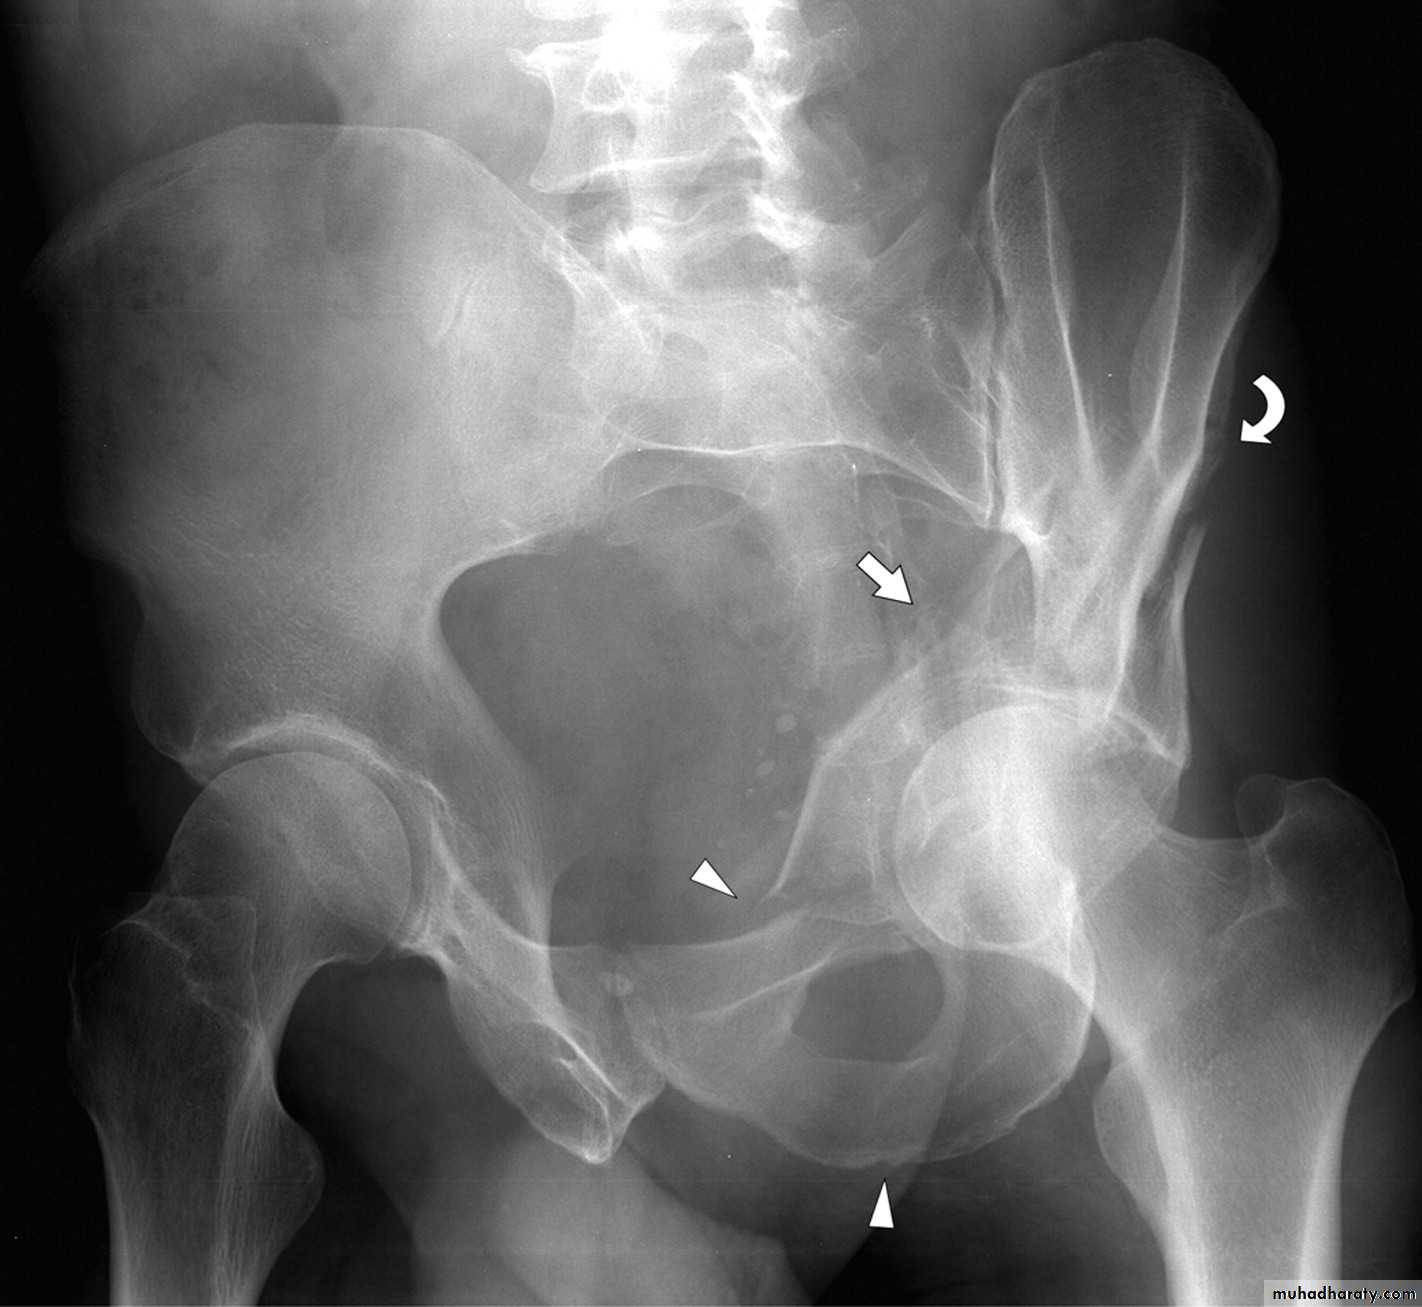

SCIATIC NERVE

Division of the main sciatic nerve is rare except.in

gunshot wounds.

Traction lesions may occur with

traumatic hip dislocationsand with pelvic fractures.

Intraneural haemorrhage in patients receiving anticoagulantsClinical features